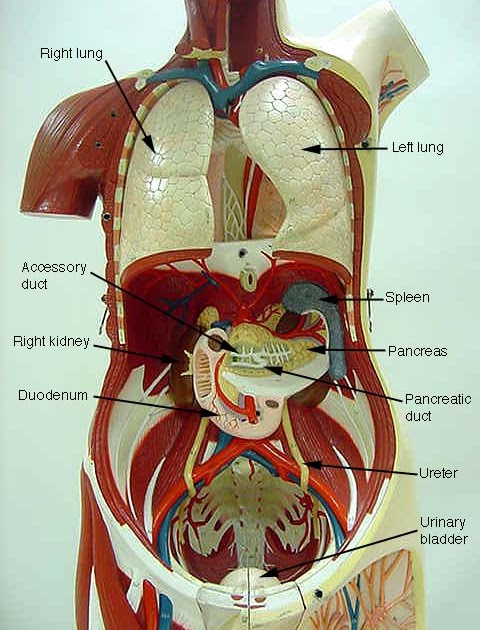

Full Female Torso Anatomy 3D model | CGTrader  Torso Model Anatomy Labeled / New Page 1 classroom.sdmesa.edu / Human tooth anatomy with labeled

Torso Model Anatomy Labeled / New Page 1 classroom.sdmesa.edu / Human tooth anatomy with labeled  Human Female Torso Anatomy 3D Model MAX OBJ 3DS FBX C4D LWO LW LWS - CGTrader.com

Torso Anatomy Chart / Torso Anatomy Chart : Anatomy Chart Trigger Point Charts - Paka Lapan  Pin by sindo vazquez on Anatomia dibujo | Anatomy sketches, Anatomy drawing, Human anatomy art

Torso Anatomy : Diagram Woman Of Upper Torso Diagram Full Version Hd Quality Torso Diagram  How to Draw the Female Torso, an in-Depth Guide â GVAAT'S WORKSHOP